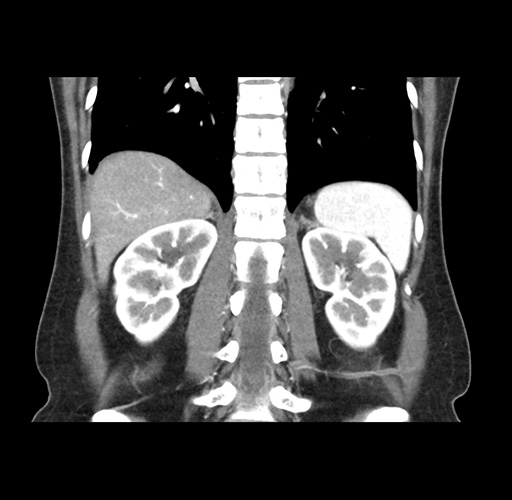

Imaging Analysis

Look through the patient's CT scan to identify any areas of concern for the necessary procedure.

Based on your CT findings, which issue(s) would give reason for "planned slowing down moment(s)" in this case?

Considering a standard left lateral sectionectomy procedure, what step(s) of the operation would you do differently in this case ?